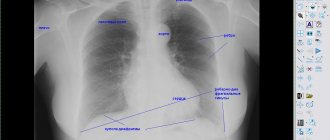

• рентген органов грудной клетки (обзорный и прицельный при обнаружении подозрительных участков);